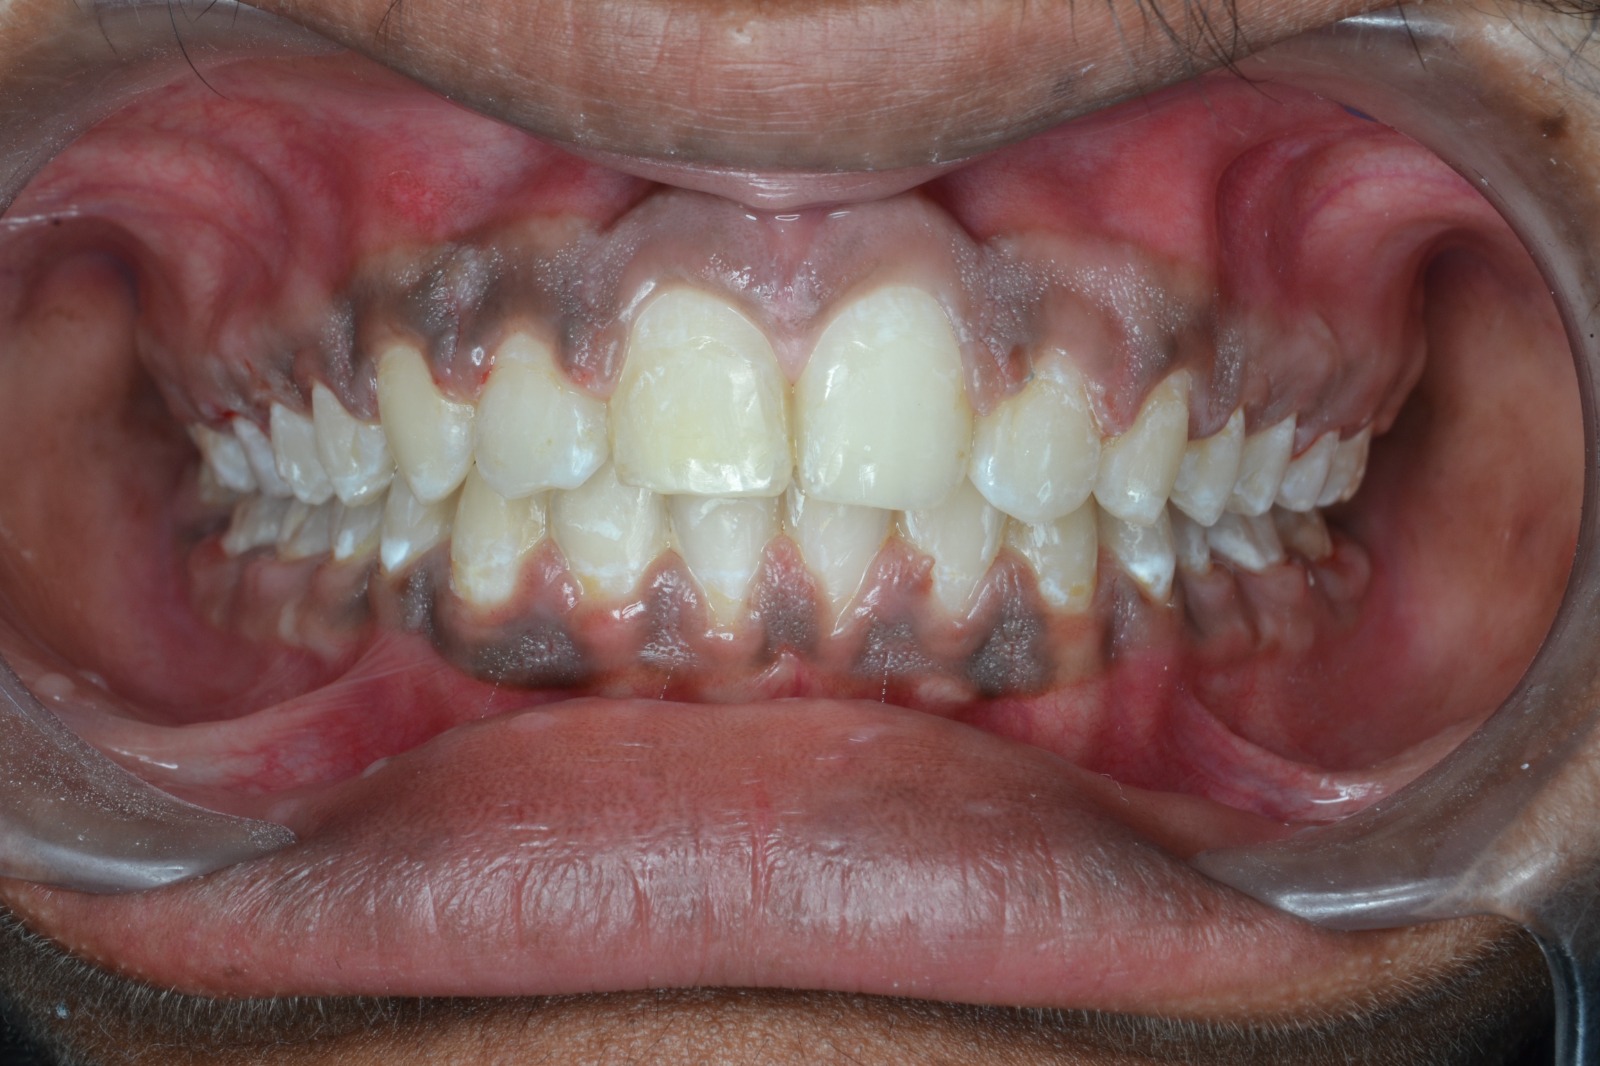

Sairam dental care located in Dharmapuri, with Leading Dentist In Oddapatti, is the Dental Hospital with exclusive root canal, Braces & Invisalign center. Led by renowned Drs Raghuraaman ( Periodontist) and Nivetha Raghuraaman ( Orthodontist) Sairam dental care offers gum treatment with expertise in laser, root canal treatment and digital smile correction with advanced technology aim to focus on aesthetics, comfort and precision. The clinic also specializes in Invisalign treatment, digital smile makeover, laser gum care, dental implants, root canal therapy, extractions and full-mouth rehabilitation blending compassionate care and clinical excellence.

Our professional, experienced, and passionate dentists make us the best choice for Invisalign treatment in Dharmapuri, providing top-notch dental services.